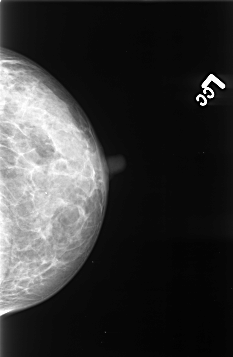

B_3422_1.LEFT_CC

LEFT_CC LINES 4280 PIXELS_PER_LINE 2792 BITS_PER_PIXEL 12 RESOLUTION 50 NON_OVERLAY